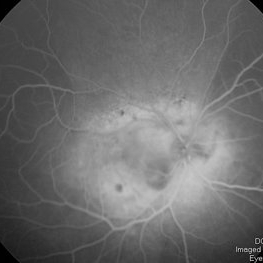

RetCam fluorescein angiogram late venous phase of diffuse choroidal hemangioma

Condition/keywords: diffuse choroidal hemangioma